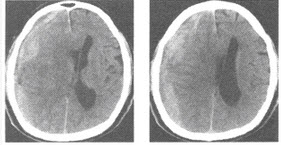

女,28岁,阴道有异常液体流下,CT和MRI扫描如图,下列说诊断正确的是()

男,53岁,吸烟史30多年,头痛,CT检查如图,最可能的诊断为()

A.转移瘤

B.脑囊虫病

C.多发结节性硬化

D.结核瘤

E.脑膜瘤